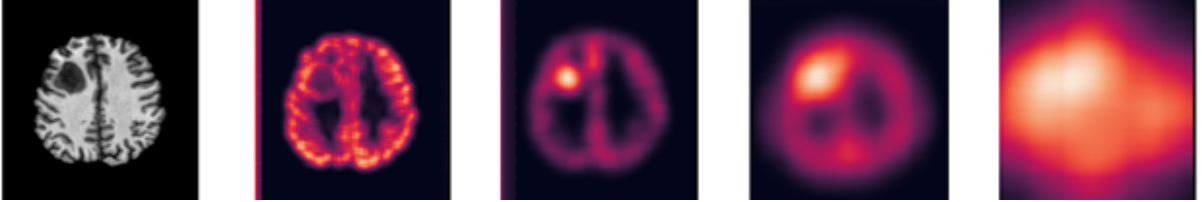

In figure 3, the heatmaps indicate higher reconstruction loss values where the tumour is present. Heatmaps produced from smaller window sizes performed better on healthy regions, whereas larger window sizes appear to localize the tumour more effectively. It is important that the window covers most if not all the tumour to distinguish the reconstruction performance with other healthy areas of the brain. However, if the size of the tumour is known beforehand, then choosing the \saybest-fit window would be preferable.